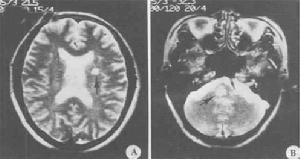

(三)MRI( magnetic resonance imaging )

常規MRI檢查對MS的臨床確診患者MRI陽性率>95%。MRI檢查可見大小不一,類似圓形的T1底信號,T2高信號,常見於側腦室前角與后角周圍,半卵圓中心及胼胝體,或為融合斑,多位於側腦室體部;腦幹、小腦和脊髓可見斑點狀不規則T1底信號及T2高信號斑塊;病程長的多數患者可伴腦室系統擴張,腦溝增寬等白質痿縮徵象。多發性硬化引起的震顫

多發性硬化——形象說明在顯微鏡鏡下,脫髓鞘是本病的主要變化,早期多從靜脈周圍開始(又名靜脈周脫髓鞘)伴血管周圍單核細胞或淋巴細胞浸潤。進行性脫髓鞘病灶的邊緣常有多量單核細胞浸潤,病灶中髓鞘變性崩解成顆粒狀,並被吞噬細胞吞噬,形成泡沫細胞。軸索大多保存,部分可因變性而發生腫脹、扭曲斷裂,甚至消失。此外,少突膠質細胞明顯減少,甚至脫失;星形膠質細胞反應性增生十分明顯,有時可出現肥胖細胞。晚期病灶膠質化,成為硬化斑。

如脫髓鞘區與有髓鞘區相互交替,形成同心圓樣結構,則稱為同心圓性硬化又名Balo病,在我國東北和西南地區有散發病例的報導。近年觀察發現,同心圓硬化和一般的脫髓鞘病灶可出現於同一病例;因此Balo病可能僅是經典型MS的某一階段的表現。Schilder病則表現為大腦皮質下白質廣泛的融合性脫髓鞘病變。皮質下弓狀纖維的髓鞘保存完好是其特徵。